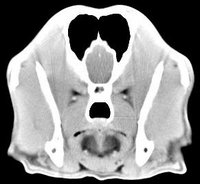

imágenes de TC en el perro | ||||||||||

ejemplo de imágenes de TC en el perro. Nótese la celulitis en la región parotídea izquierda | ||||||||||